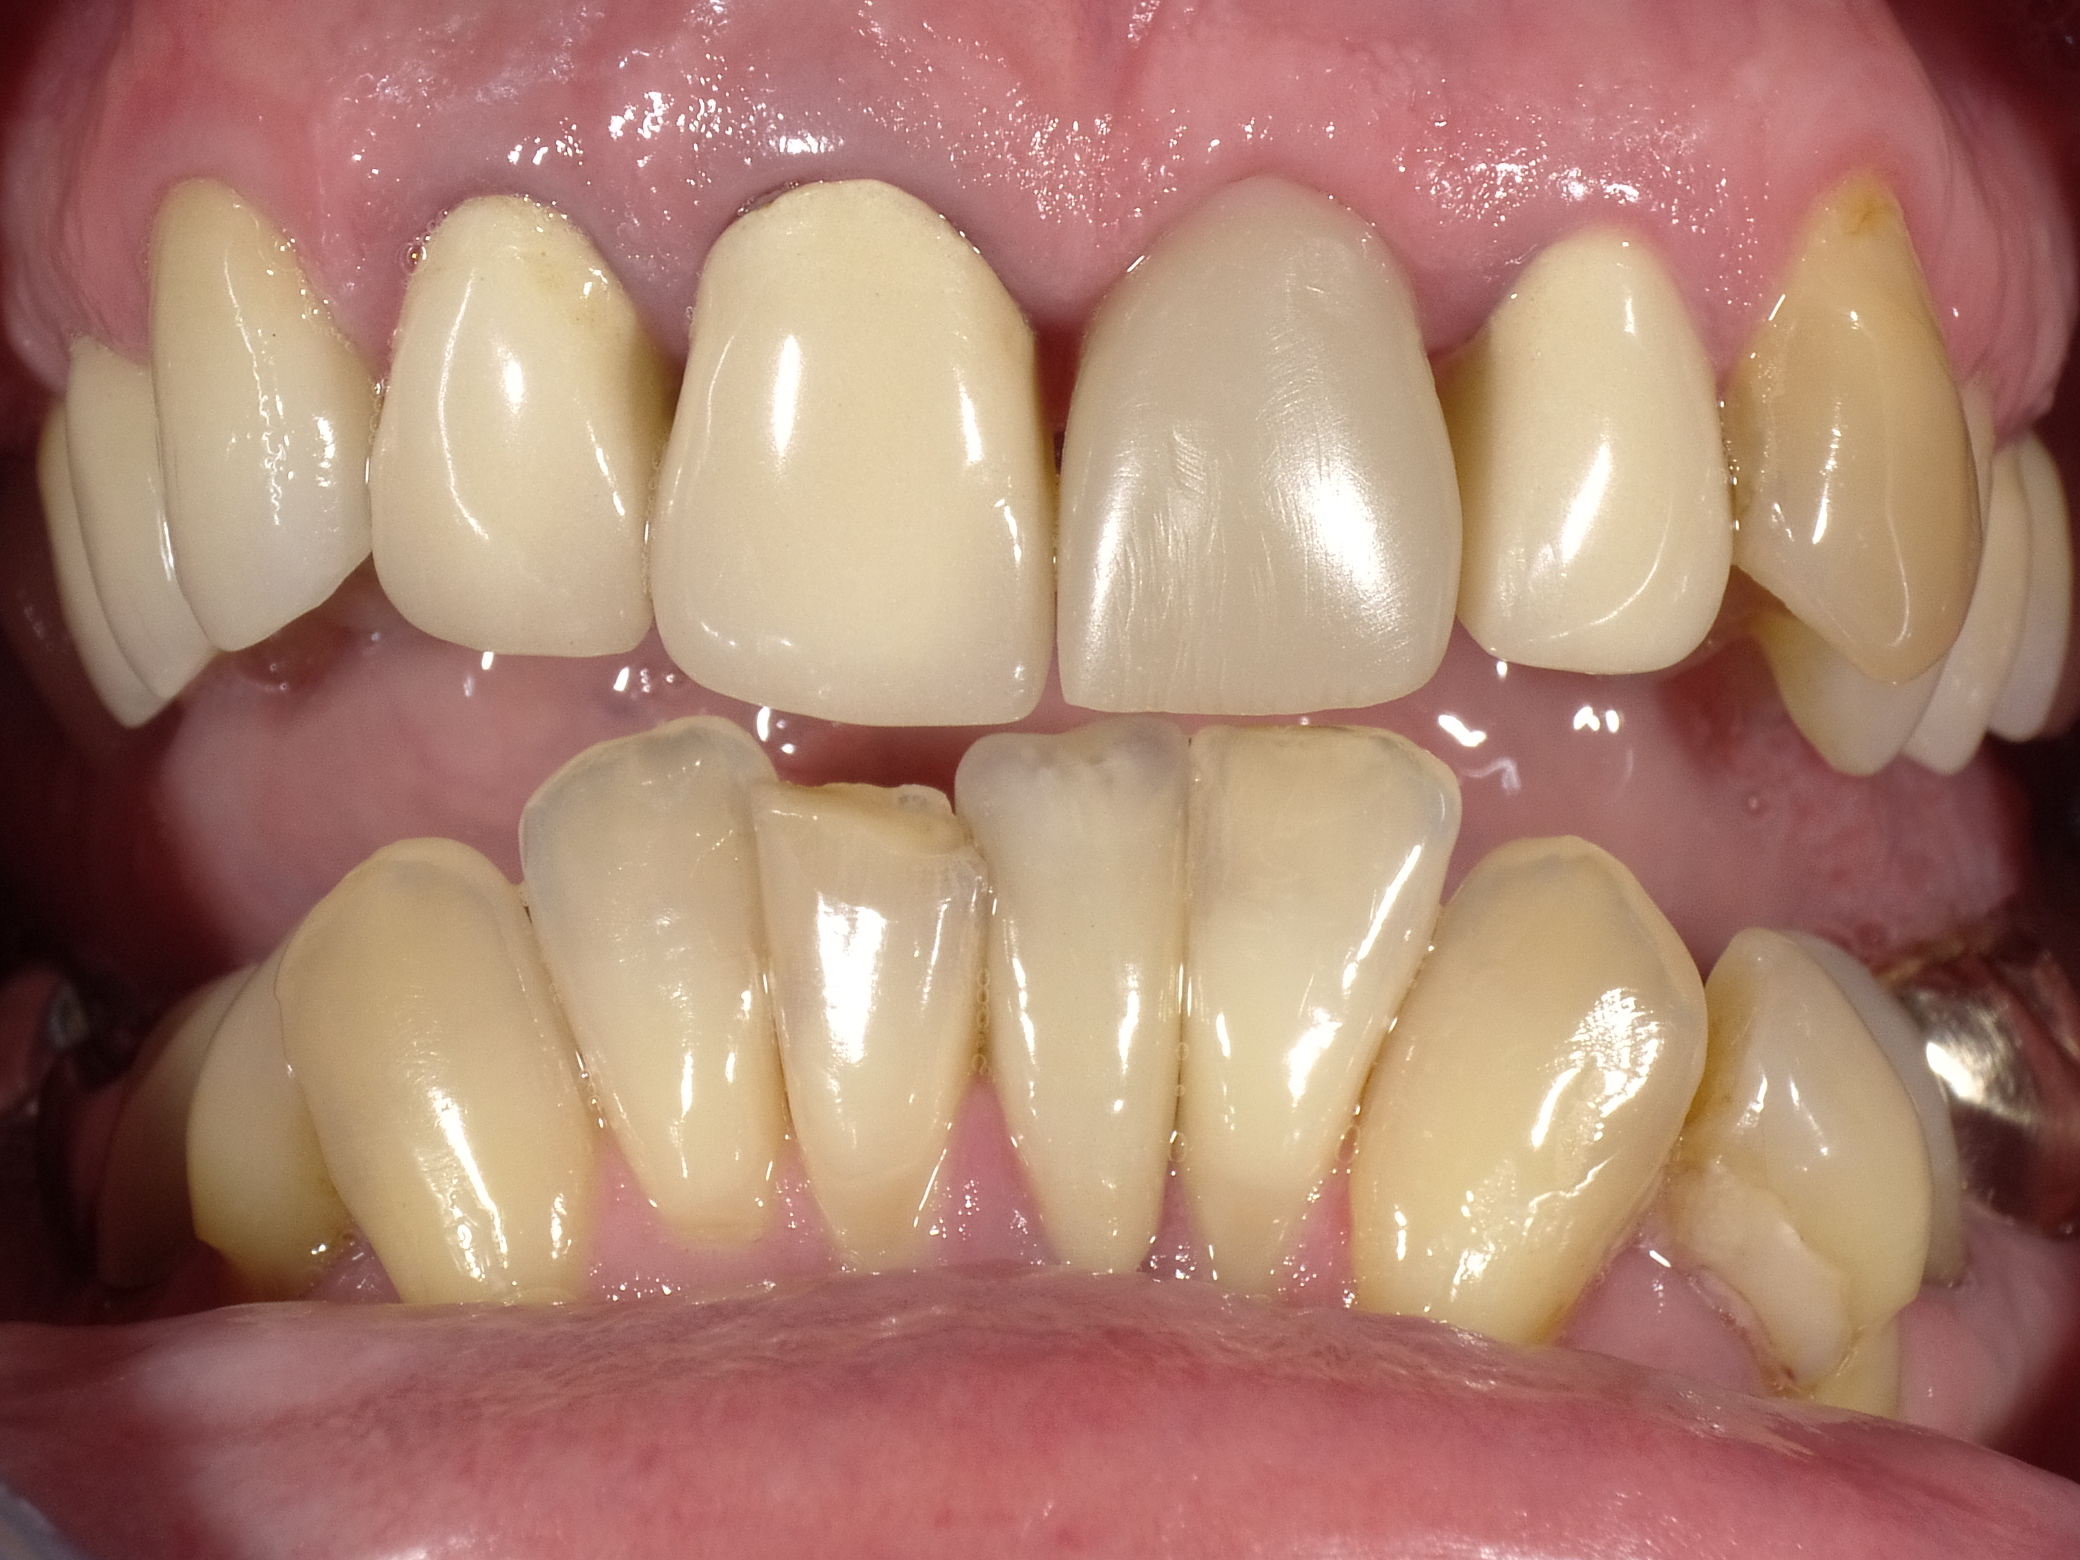

Unbefriedigende Ästhetik, vor allem aber Entzündungen im Knochen und eine massive Parodontitis mit bereits gelockerten Zähnen

Vorher: Unbefriedigende Ästhetik, vor allem aber Entzündungen im Knochen und eine massive Parodontitis mit bereits gelockerten Zähnen

Gesamtbehandlung in Sedierung: die Seitenzähne wurden durch Keramik-Implantate (Zahnentfernungen und Sofortimplantation) mit Knochenaufbau ersetzt; anschließend Gesamtüberkronung aus Vollkeramik mit Optimierung der Ästhetik

Nachher: Gesamtbehandlung in Sedierung: die Seitenzähne wurden durch Keramik-Implantate (Zahnentfernungen und Sofortimplantation) mit Knochenaufbau ersetzt; anschließend Gesamtüberkronung aus Vollkeramik mit Optimierung der Ästhetik